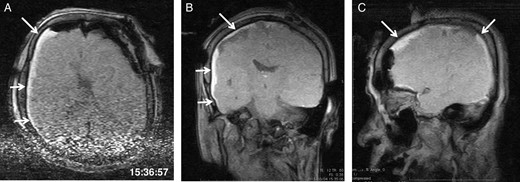

General anaesthesia was induced. Following left frontal craniotomy and dural incision, the first iMRI was performed (Fig. 1 ). One hundred fifty-eight minutes from induction, the patient regained consciousness after all anaesthetics were ceased. Tumour resection was performed with free conversation. However, after 143 min of surgery under the awake condition, the patient came to complain of excessive sleepiness though she could respond to verbal commands. Electrocorticogram (ECoG) did not detect after-discharge. The tumour was successfully removed en bloc fashion. Progressive brain swelling was not observed. The second iMRI was commenced 182 min into the awake phase (Fig. 2). Thirteen minutes from the beginning of the second iMRI scanning, the patient did not respond to noxious stimuli. When the patient was removed from the gantry, she was unconscious and had stopped spontaneous breathing. Her pupils were isocoria and did not dilate. Neither epileptic seizure nor anaphylactic reaction occurred. The peripheral oxygen saturation was not measurable, but cardiac instability or signs of vomiting were not observed. We decided to discontinue the operation under the awake status. No electrolyte imbalance or hypoglycaemia was observed. Subsequently performed iMRI identified a thin subdural haematoma in the contralateral side (Fig. 3). The fourth iMRI confirmed that most of the haematoma was evacuated following right frontal craniotomy.

The first intraoperative magnetic resonance images performed after the craniotomy. (A) Axial, (B) coronal and (C) sagittal T1-weighted scout images show the left frontal tumour. The time of scan is superimposed.